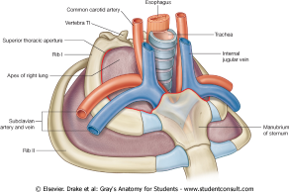

show what the superior thoracic aperture and inferior thoracic aperture are?

notice how in the first picture the esophagus and trachea, nerves and BV's are popping through

what does the superior thoracic aperture contain?

what does the inferior thoracic aperture allow?

- Superior...contains esophagus, trachea, nerves & blood vessels that supply the head, neck and UE

- Inferior...allows the esophagus, IVC (inferior vena cava) and aorta to pass inferior to abdominal cavity